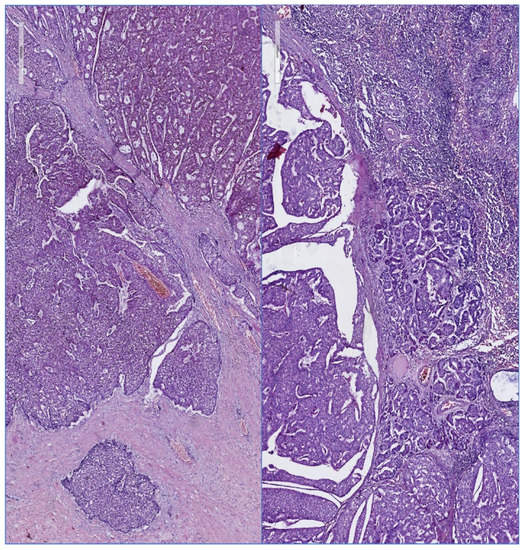

3.1.5. Pathology

- Shaaban, A.M. Pathology of the male breast. Diagn. Histopathol. 2019, 25, 138–142. [Google Scholar] [CrossRef]

- Zhong, E.; Cheng, E.; Goldfischer, M.; Hoda, S.A. Papillary Lesions of the Male Breast: A Study of 117 Cases and Brief Review of the Literature Demonstrate a Broad Clinicopathologic Spectrum. Am. J. Surg. Pathol. 2020, 44, 68–76. [Google Scholar] [CrossRef]

- Avau, F.; Chintinne, M.; Baudry, S.; Buxant, F. Literature review and case report of bilateral intracystic papillary carcinoma associated with an invasive ductal carcinoma in a male breast. Breast Dis. 2022, 41, 5–13. [Google Scholar] [CrossRef]